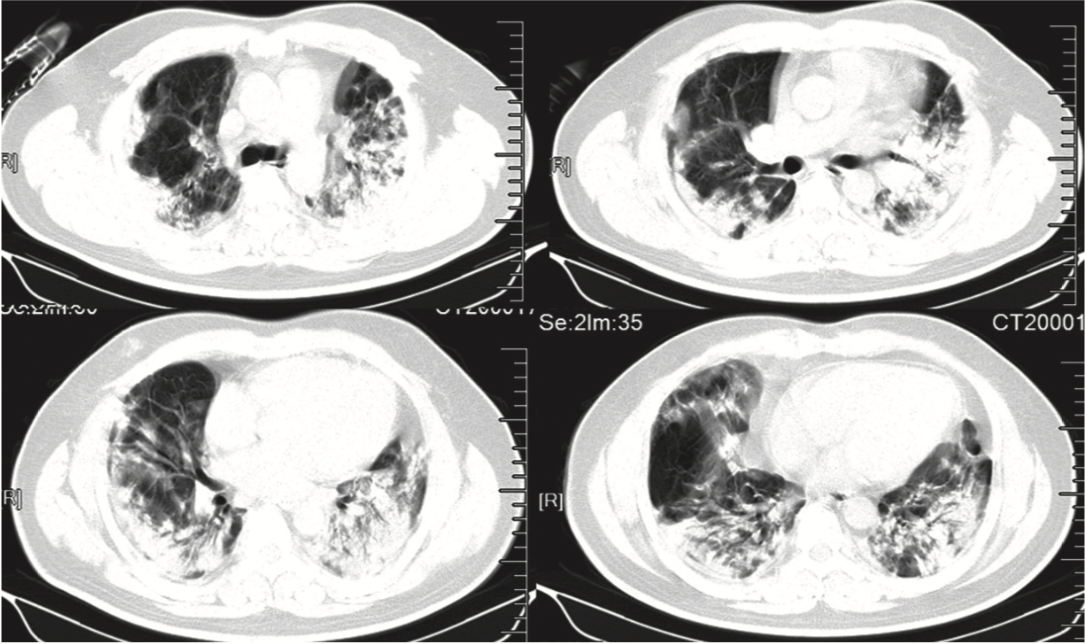

Transverse chest CT images from a 40-year-old man showing bilateral multiple lobular and subsegmental areas of consolidation on day 15 after symptom onset. Photo: January 24, 2020; https://doi.org/10.1016/ S0140-6736(20)30183-5; LANCET

The 2019-nCoC attacks the lungs with development of multiple pneumonia in both lungs. Soon the lungs adopt a ground glass appearance on a CT scan. This is when matters have gotten very grim for the patient can now die. There is no specific treatment, management being supportive. Treat fever with paracetamol, and when the lungs begin to fail intubate the patient and attach him to a mechanical ventilator, hoping for the best.